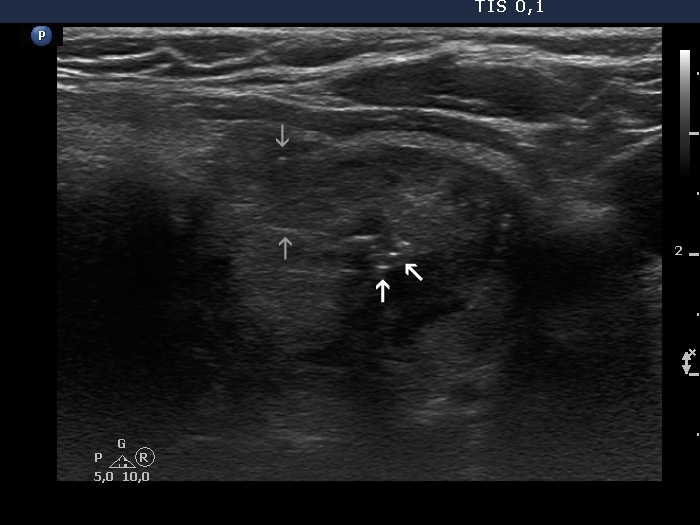

Benign colloid goiter (cytological diagnosis)

The nodule has both pale and bright hyperechogenic lines and granules. Arrowheads point to figures representing the normal architecture of the thyroid while arrows do to thickened connective tissue.